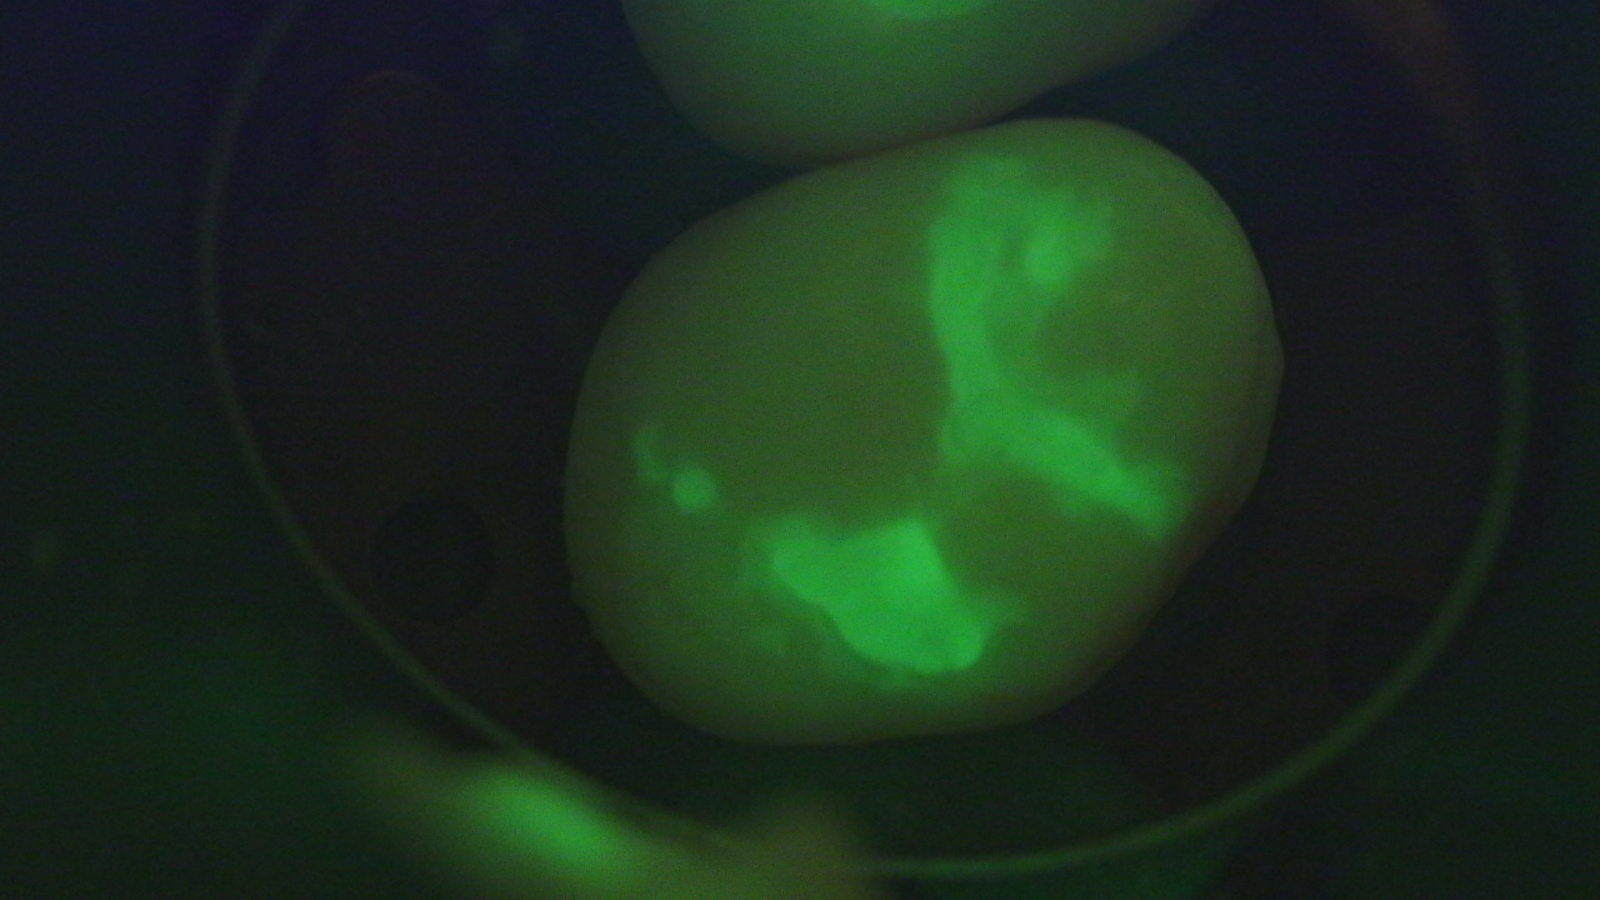

А вот так его видно в микроскоп:

image

Видите? Канал чистый.

Микроскоп даёт возможность смотреть на зуб в разных диапазонах, в том числе в ультрафиолете. Вот тут видны реставрационные материалы. А вот вам пример обычного снимка:

И аналогичный поиск кариеса с окрашивающей подсветкой:

Полезно иметь такое прямо в операционном микроскопе, чтобы не убирать лишние ткани. Это не суперпрорыв, но очень удобно.